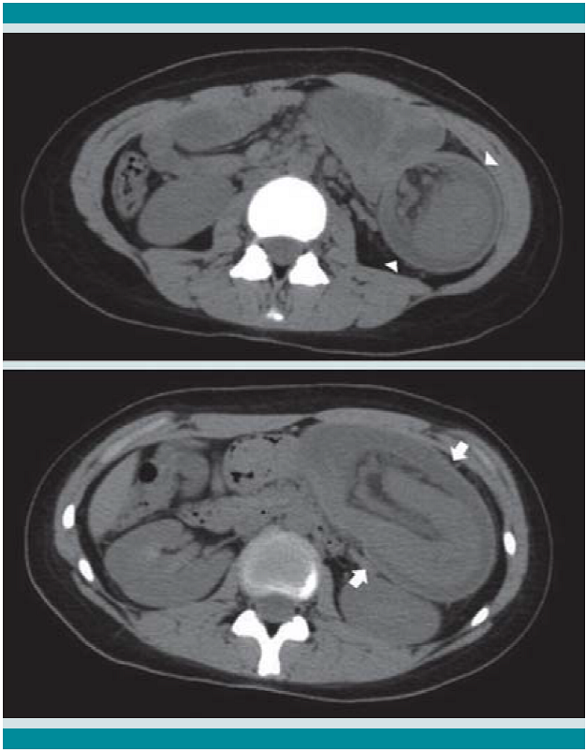

El ultrasonido abdominal sugirió probable invaginación intestinal; posteriormente se corroboró con tomografía computada de abdomen, al observar el "signo de la rosquilla", imagen característica en diana, con bandas de diferente densidad concéntricas, en relación con las paredes del asa del intestino que se introducían dentro de su propia luz. (Figura 2)